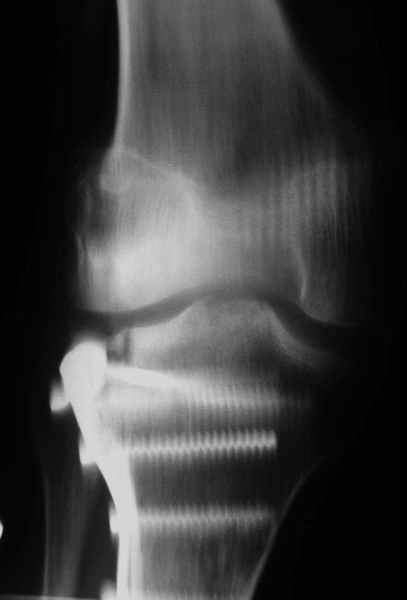

Относительно "рубцовой подушки" я имел в виду остатки мениска ( частично вколоченного в дефект мыщелка и фрагменты хряща), все таки на рентгенограммах суставная щель в этом отделе чем то заполнена. Что касается некроза мыщелка бедра, то мне кажется он уже наступил - томограмма ноябрь5.

С учетом всего сказанного - наличия прогессирующего вальгуса конечности, довольно приличного объема движений, имеющегося, вероятно, некроза мыщелка бедра, наиболее рациональным представляется удалить пластину с б\б кости, произвести остеотомию б\б кости с коррекцией вальгуса, разгрузив тем самым наружный отдел сустава, и синтезировать фрагменты голени накостным фиксатором. Максимально тано начать восстановление движений в суставе. Скорее всего рано или поздно речь о протезировании всеже возникнет, но мы хотя бы будем иметь приличную ось конечности.

С *вколоченным* мениском встречаться не приходилось, нередко при импрессионных переломах наблюдал центральную дислокацию мениска по типу bucket handle, что в этой ситуации может объяснить сгибание сустава до 90 и разгибание 160 градусов, отчасти невозможность полностью разогнуть ногу при Рг графии сустава затрудняет интерпретацию прямой проекции сустава.

Сканирование с Тс99 поможет верифицировать наличие некроза мыщелка бедра, если использовались титановые винты, то магнитно-резонансное исследование будет более информативным. При подтверждении некроза, бедренная или всокая тибиальная остеотомии, очевидно, будут малоуспешны, поэтому альтернатив артропластике похоже не останется. Наблюдений реваскуляризации мыщелка бедра после туннелизации у меня нет, надо покопаться в литературе.

Тут ситуация совсем другая. Деформация не около-, а самая что ни на есть внутрисуставная. Покорректировать внешний вид конечности путем остеотомии дистального отдела бедра и high tibia (плюс или минус клин, одномоментно-постепенно, аппарат-пластина-стержень - дело третье) не сильно сложно, но это не решение проблемы. У больной, по

сути отсуствует латеральный отдел коленного сустава, что требует костно-пластических вмешательств непосредственно на артикулирующих

поверхностях.

Может быть, целесообразней сразу протез, чем тот же протез, но после сложных, но сомнительно результативных операций типа замещения алломыщелком, моделирующих резекций и т.п.? Ну и в любом случае движения лучше бы разработать получше до любой операции.